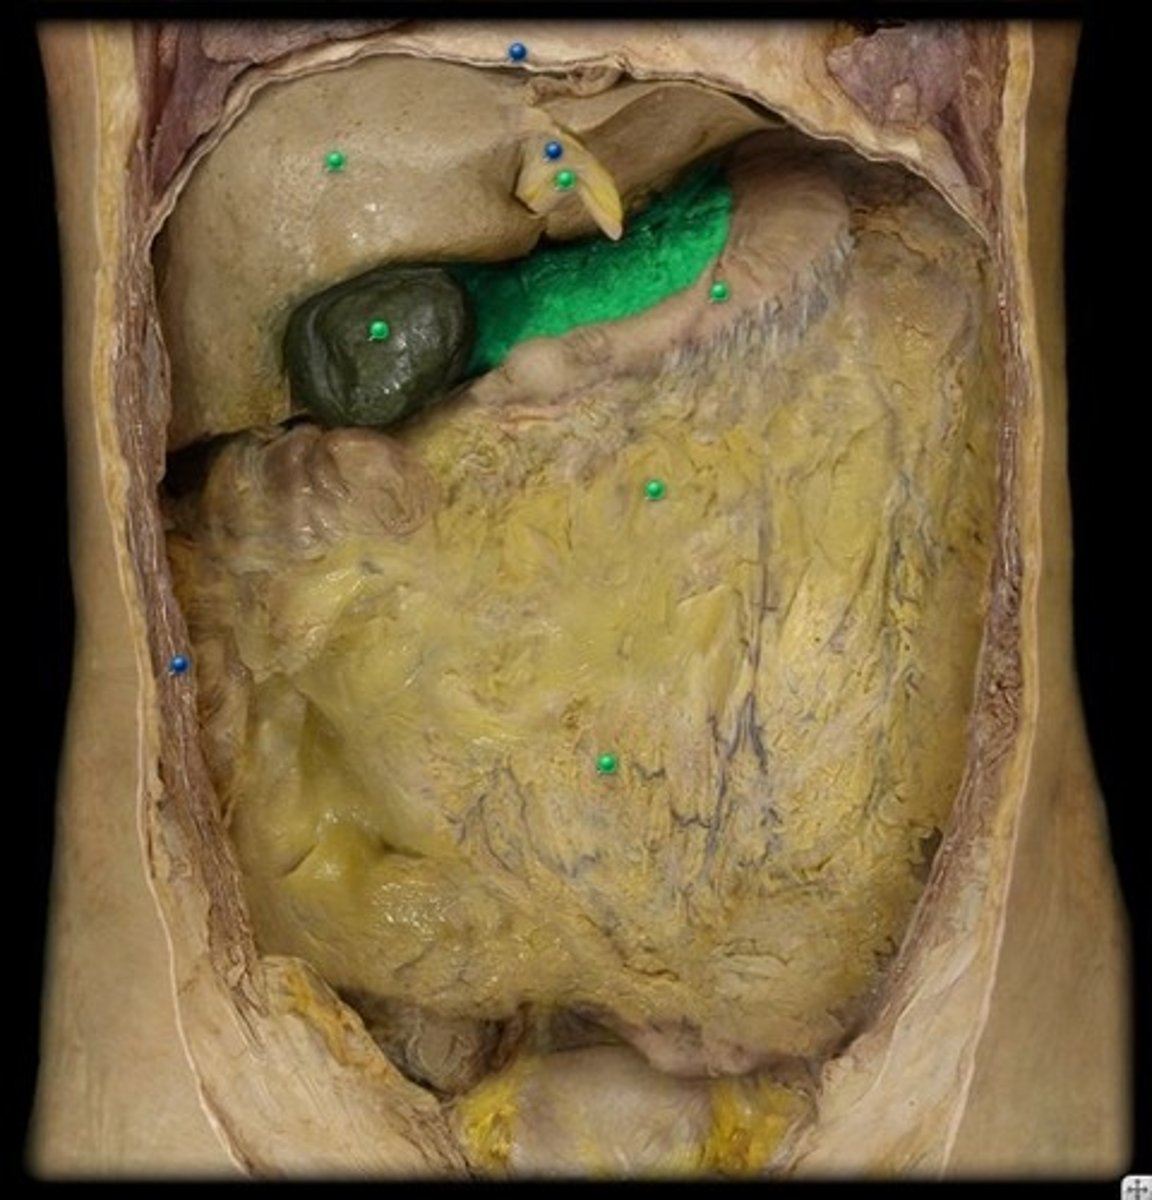

Diaphragm

Right Lobe of Liver

Gall Bladder

Greater Omentum

Lesser Omentum

Head (of Pancreas)

Body (of Pancreas)

Tail (of Pancreas)

Spleen